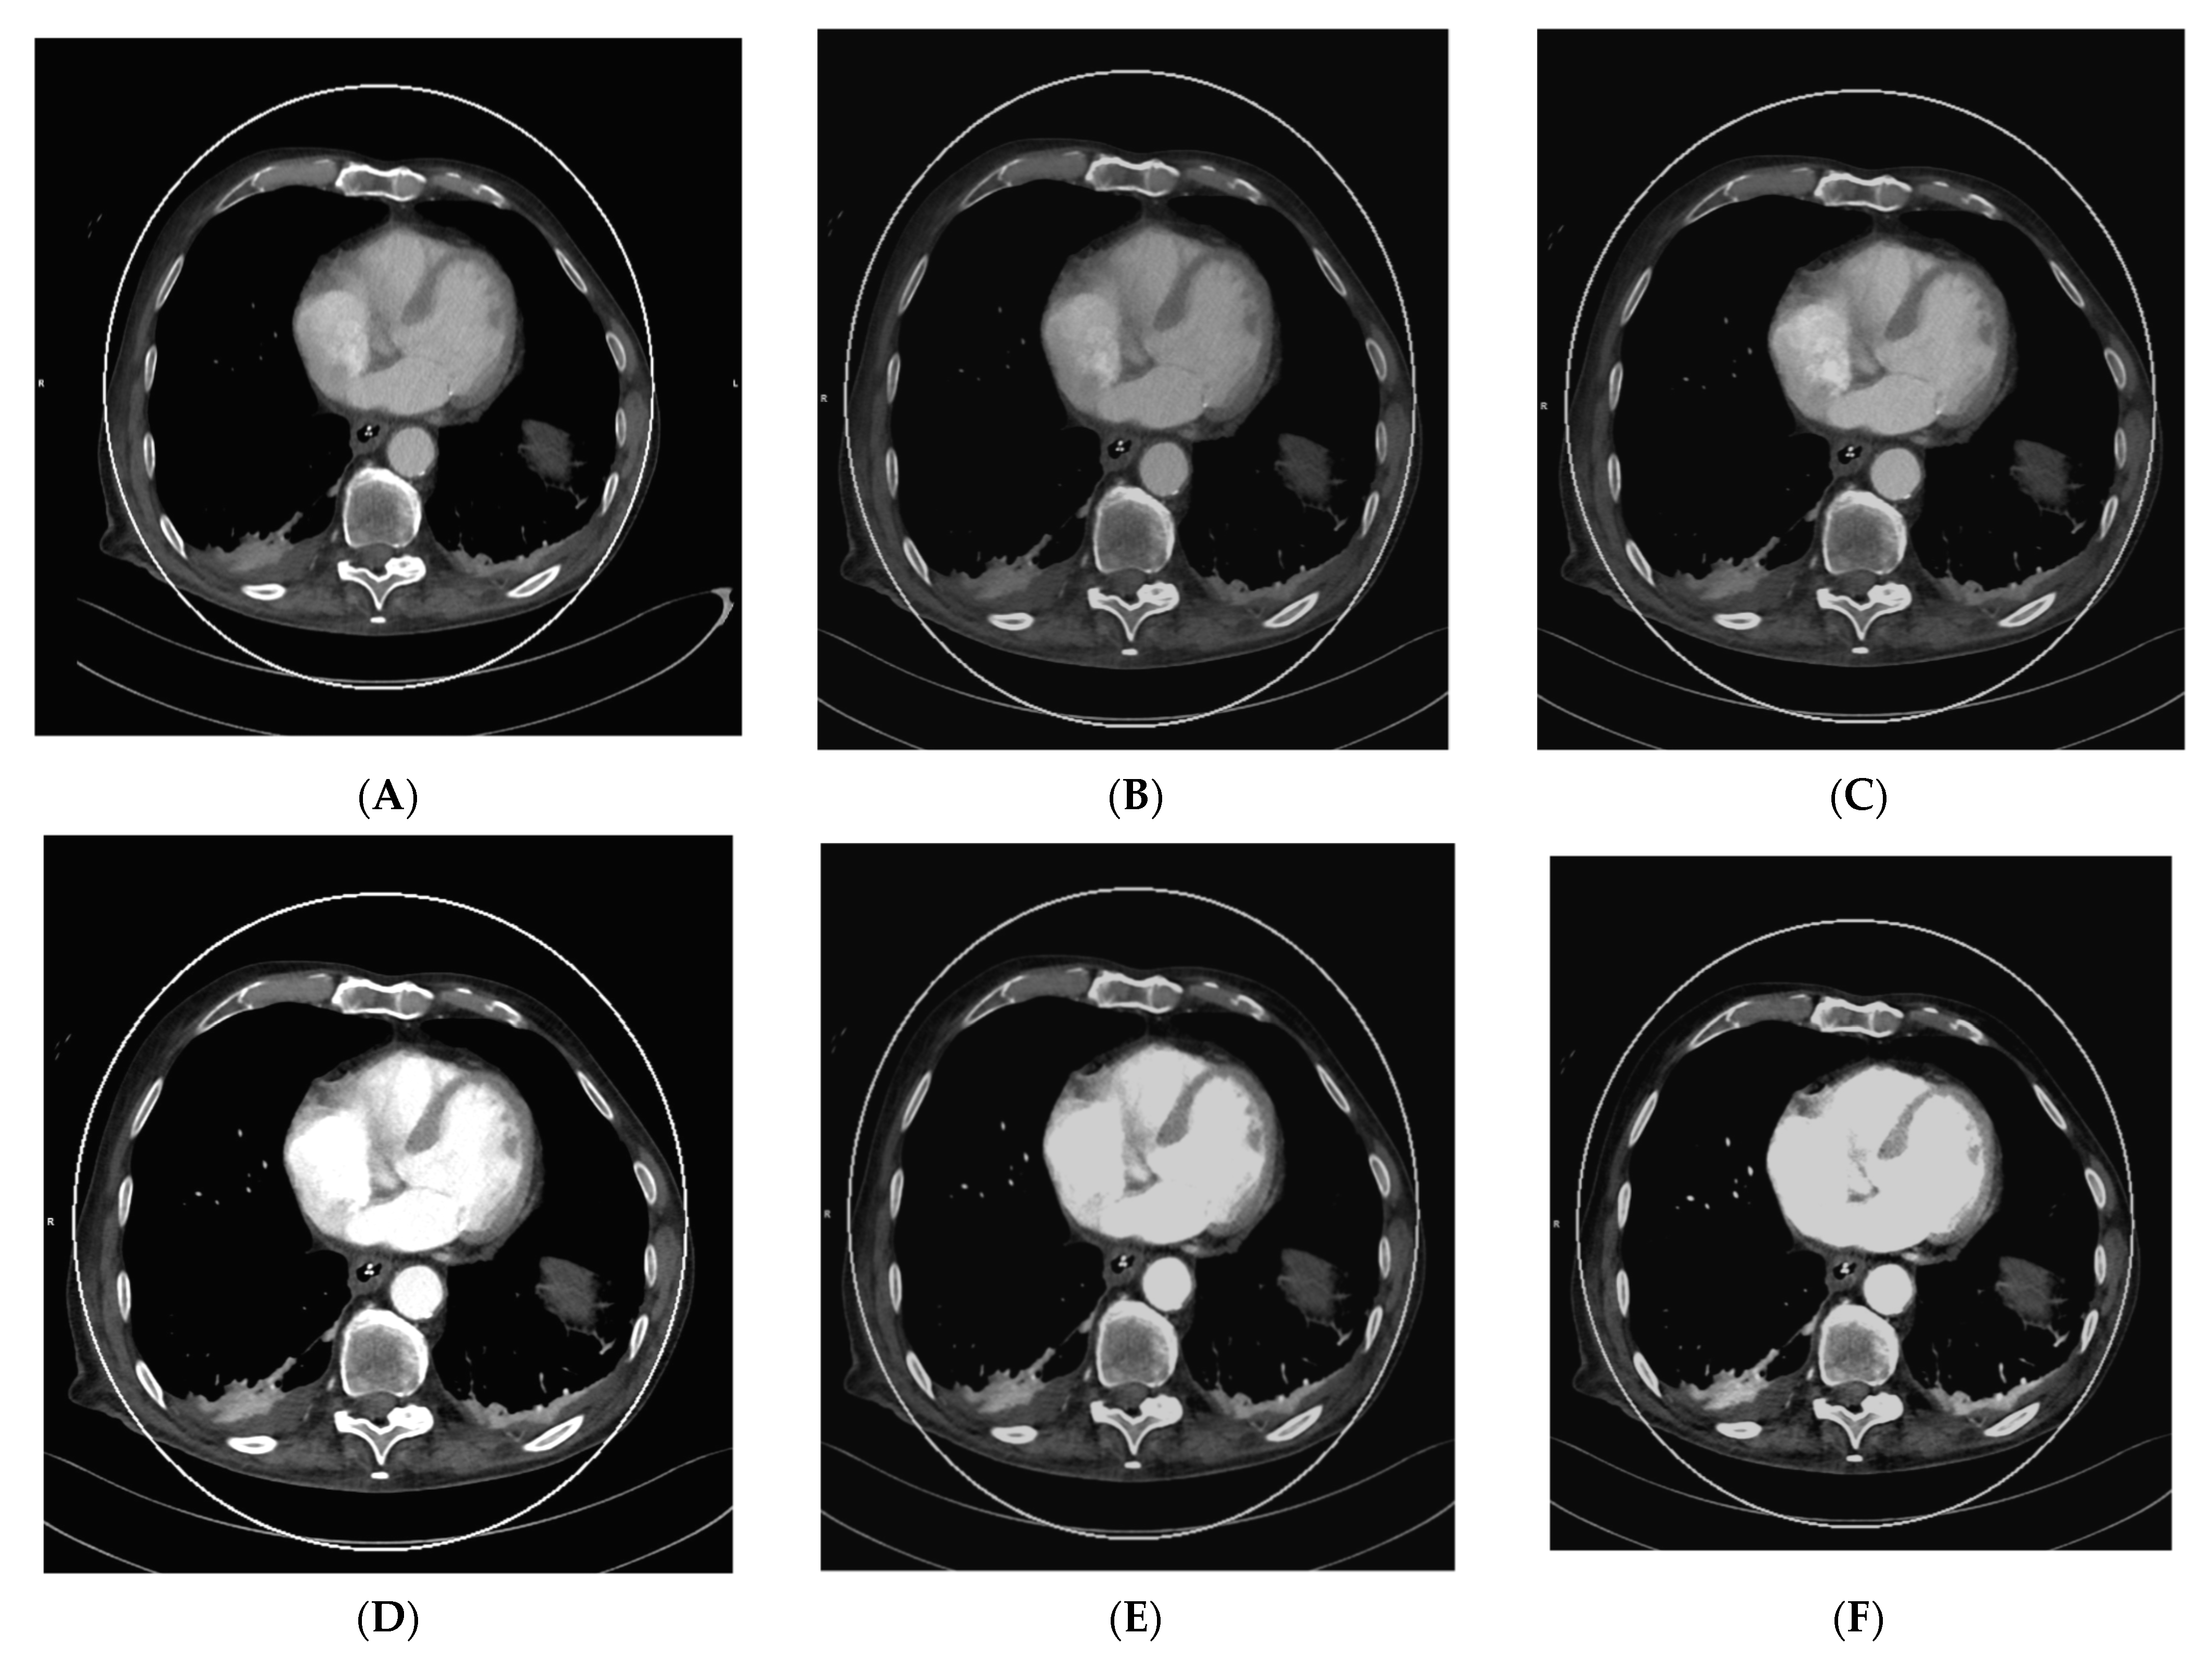

As vascular applications were one of the first fields where the benefits of DECT were demonstrated in studies and applied to routine clinical practice, aortic imaging is one of the essential fields in this context. Using DECT, it is possible to explore the effect of low-kV acquisitions using the K-edge of iodine for improved contrast in series. Martin et al. (2017), Albrecht et al. (2016), and others described that enhanced iodine contrast allows for improved detection of endoleaks; for example, in the context of thoracal or abdominal endovascular aortic repairs thoracic endovascular aortic repair (TEVAR), endovascular aneurysm repair (EVAR), fenestrated endovascular aneurysm repair (FEVAR), as well as insufficiencies and leakage of surgically implemented grafts [17,51,52,53]. Furthermore, this technique can compensate for the missed bolus and insufficient concentrations of iodine to a certain degree. The literature described that the contrast agent amount could be reduced by up to 50% in the vasculature by using 50 kV reconstructions [26]. This could be especially relevant to patients with impaired renal function, which is often associated with generalized vascular disease; however, the low-kV images also have more image noise owing to the higher rate of interaction of the photons with the atoms of the scanned body, which varies in severity depending on the DECT hardware used [6]. Figure 1 shows a case of low intravascular iodine contrast, which was caused by low-output cardiac function, as seen in the VMI reconstruction at 120 kV (Figure 1A).

Figure 1.

Acquisition of a DECT CTA of the thoracic aorta with a bad intravascular contrastation due to low output cardiac insufficiency in a 75-year-old male patient suffering from chest pain, tachycardia, and peripheral edema; (A) shows an axial view 120 kV VMI reconstruction of the descending aorta thoracalis with low intravascular contrast. Further, we see bilateral pleural effusions with adjacent partial atelectasis of the lung parenchyma. Aortic dissection could be ruled out as a cause for the clinical presentation; (B–G) show monoenergetic VMI reconstructions from 40 to 90 kV in 10 kV steps, with increasing contrast from the higher kV reconstruction of 90 kV (B) to the low-kV reconstructions with maximum intravasal contrast in the 40 kV reconstruction (G), which is closest to the K-edge of iodine, which is located at 33 kV. Accordingly, the K-edge peak is found in (G), as the highest intravasal attenuation is found here.

Consequently, VMI reconstruction was used to optimize intravascular contrast by generating monoenergetic reconstructions from 40–90 kV in 10 kV steps (Figure 1B–G, with the maximum contrast visible in the VMI 40 kV reconstruction (Figure 1G). This is especially important in the context of the visibility of small vessels, bleeding, and low-attenuation lesions. Furthermore, iodine mapping can be used to prove the accumulation of extravasal iodine in hematomas and bleeding. Using mixed images, for example, 120 kV, which is calculated from the high- and low-kV images, can improve the image noise. Furthermore, it is possible to create virtual unenhanced images or use other material-specific applications that are derived from (virtual) monoenergetic images. These monoenergetic images can be reconstructed at 40–190 kV for DSCT DECT. In this context, calcium subtraction from calcified plaques is important [17,20].

As the images are all reconstructed from the same raw dataset, it is also possible to use subtraction and fusion techniques. A 2:1 ratio of high-kV images to low-kV images was used for composite images, as the noise in the low-kV images significantly influenced the overall image noise [6].